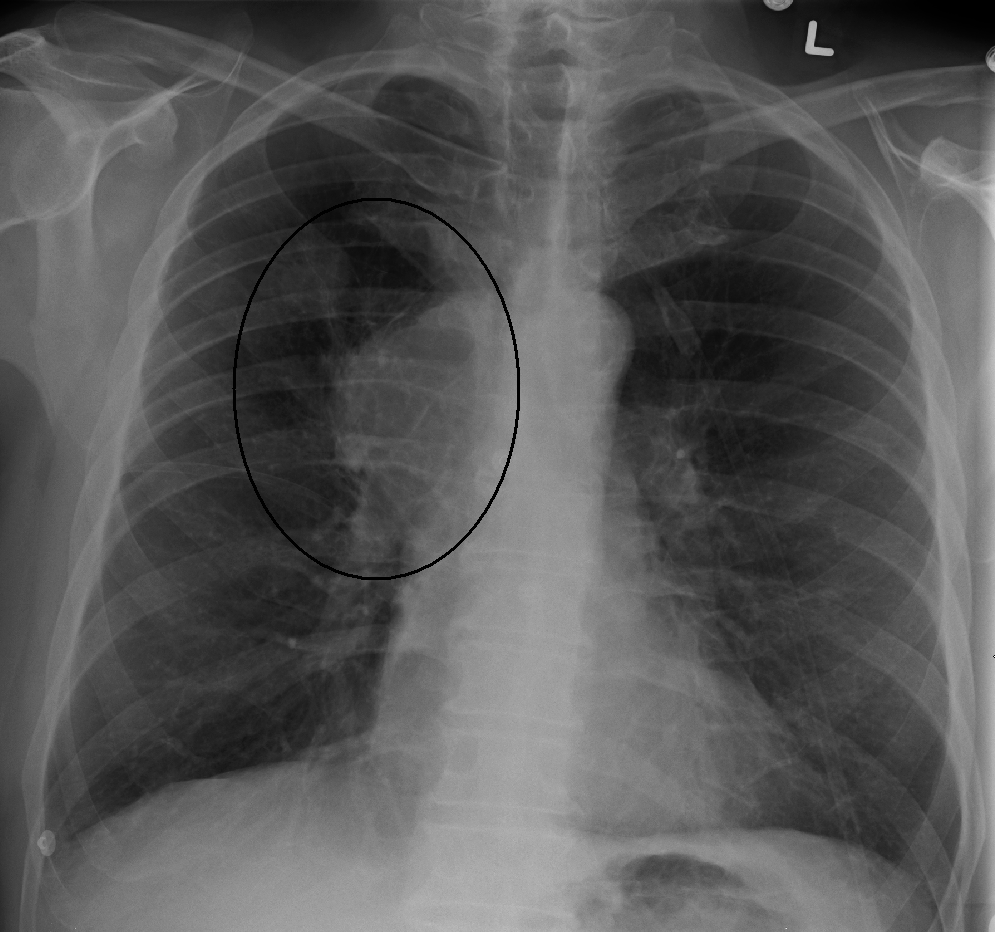

상대정맥 증후군(SVCS)을 진단하는 주요 기술에는 흉부 X-레이, CT 스캔, 기관지 내시경 검사 시 경기관지 바늘 흡인 및 종격동경 검사가 있다.[7] 흉부 X-레이는 종격동 확장을 보여줄 수 있으며, 상대정맥 증후군의 주된 원인을 나타낼 수 있다.[7] 그러나 상대정맥 증후군 환자의 16%는 정상적인 흉부 X-레이 소견을 보인다. CT 스캔은 조영 증강을 해야 하며, 목, 가슴, 하복부 및 골반에 대해 촬영해야 한다.[7] CT 스캔은 또한 근본적인 원인과 질병의 진행 정도를 보여줄 수 있다.[7]